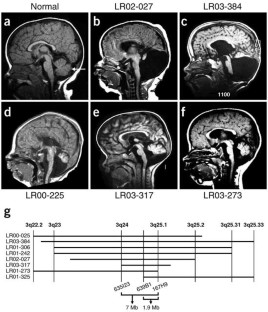

Dandy-Walker malformation (DWM; OMIM #220200) is a common but poorly understood congenital cerebellar malformation in humans. Through physical mapping of 3q2 interstitial deletions in several individuals with DWM, we defined the first critical region associated with DWM, encompassing two adjacent Zinc finger in cerebellum genes, ZIC1 and ZIC4. Mice with a heterozygous deletion of these two linked genes have a phenotype that closely resembles DWM, providing a mouse model for this malformation.

Axial CT scan from patient LR01-325. (PDF 82 kb)

In situ analysis showing Zic1 and Zic4 expression in the developing CNS, including the developing cerebellum. (PDF 165 kb)

Altered expression of ZIC1 and ZIC4 in patient LR01-325. (PDF 78 kb)

Vermis as a percentage of hemisphere width for each genotype at P22. (PDF 51 kb)

Phenotype summary of patients with del 3q2. (PDF 2 kb)